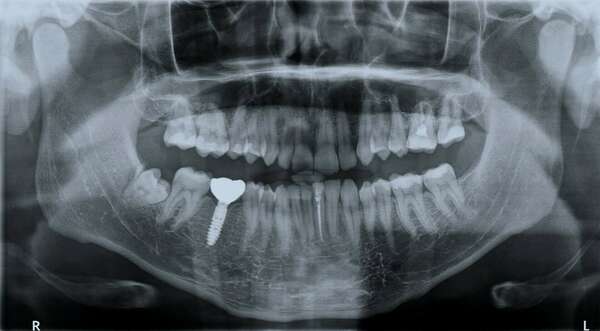

Une radio panoramique dentaire est un cliché de l'ensemble de la denture et des articulations temporo-mandibulaires.